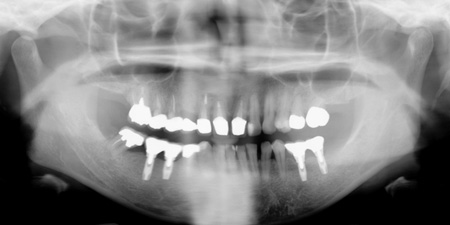

43歳 女性

主訴 奥歯で物が咬めない

治療内容 歯周病治療 咬合治療 インプラント治療 歯内治療(根の治療)

治療後